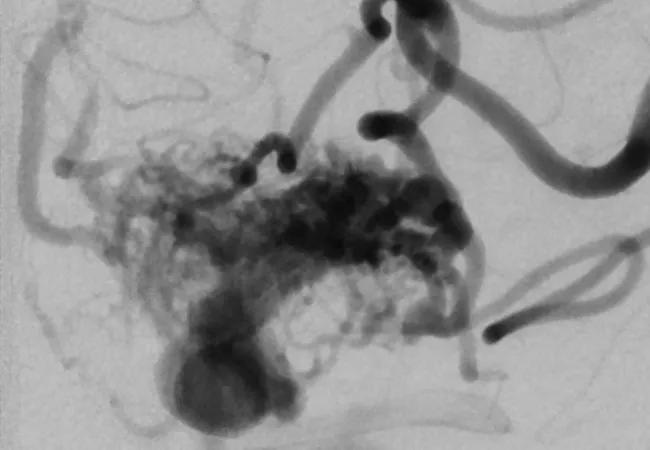

Surgical treatment of unruptured brain arteriovenous malformation (ubAVM) is associated with a lower risk of stroke or death than a watch-and-wait approach, according to a new retrospective analysis of a large series of cases at Cleveland Clinic. These results add to the controversy generated with the 2014 publication of the Randomized Trial of Unruptured Brain Arteriovenous Malformations (ARUBA),1 which came to the opposite conclusion. Our retrospective analysis of 105 patients between 2001 and 2014 who would have qualified for ARUBA was recently published in Neurosurgery.2

Optimal management of ubAVMs has been a topic of debate since brain imaging made possible the diagnosis of this often asymptomatic or mildly symptomatic condition (an example angiogram of such an AVM is shown at the top of this post). A no-treatment strategy entails a 2 percent to 5 percent annual risk of rupture. While this may seem low, over many years the cumulative chances become daunting. And the outcomes can be devastating: About one-third of patients with a bleed end up in a nursing home, and 10 percent die. But treatment is also not without risk.